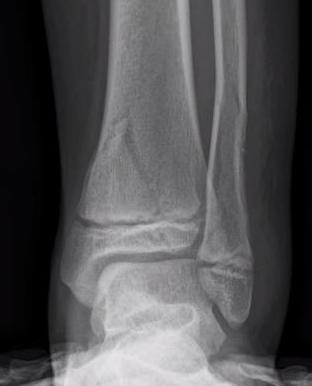

Triplanar Fracture

Definition

Fracture in coronal, sagittal and transverse planes

- crosses epiphysis

- passes through growth plate

- extends into metaphysis

Xray

AP xray: Salter-Harris type III / Tillaux

Lateral xray: Salter-Harris Type II

CT

Coronal images: Salter-Harris type III

Sagittal images: Salter-Harris type II

Axial images: 3 point star